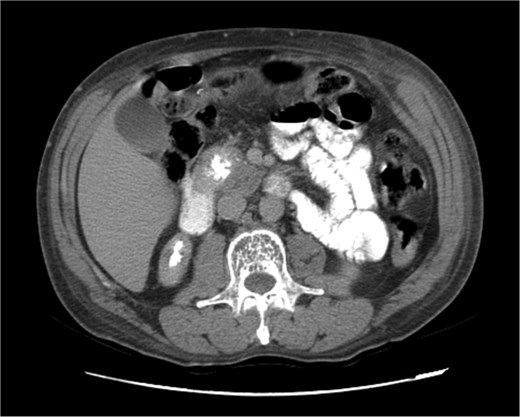

Upon admission in January 2025, the patient presented with altered mental status, dehydration, and hypoglycemia. The recurrence of hypoglycemic episodes was confirmed by laboratory studies and imaging, which identified a well-defined 3 cm mass in the pancreatic head on triphasic computed tomography (Figs 1–3). Given the diagnosis of recurrent malignant insulinoma and the possibility of resection, a surgical approach was chosen.

Triphasic computed tomography of the pancreas, late phase, showing a tumor in the head of the pancreas.